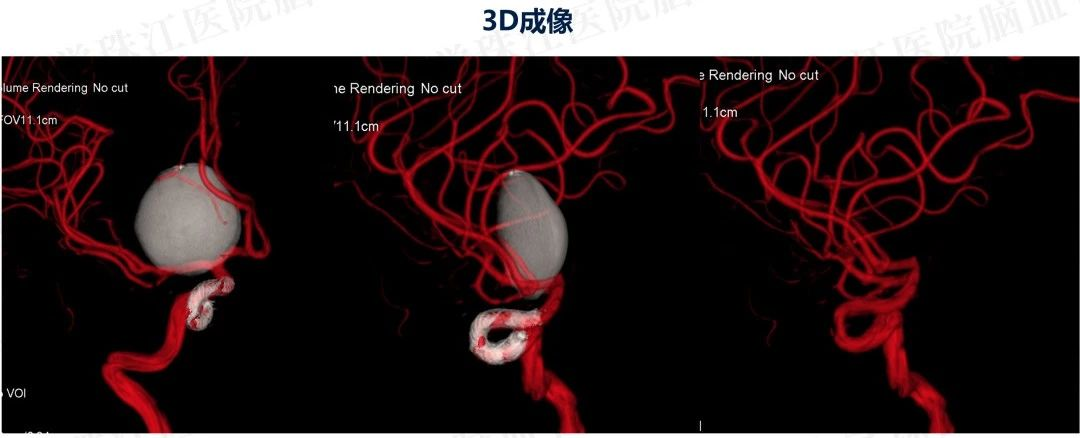

患者入院后造影发现“颈内动脉床突上段巨大动脉瘤,大小约2.7x3.5cm。决定行PIPELINES密网支架植入治疗。

患者入院后造影发现“颈内动脉床突上段巨大动脉瘤,大小约2.7x3.5cm。决定行PIPELINES密网支架植入治疗。